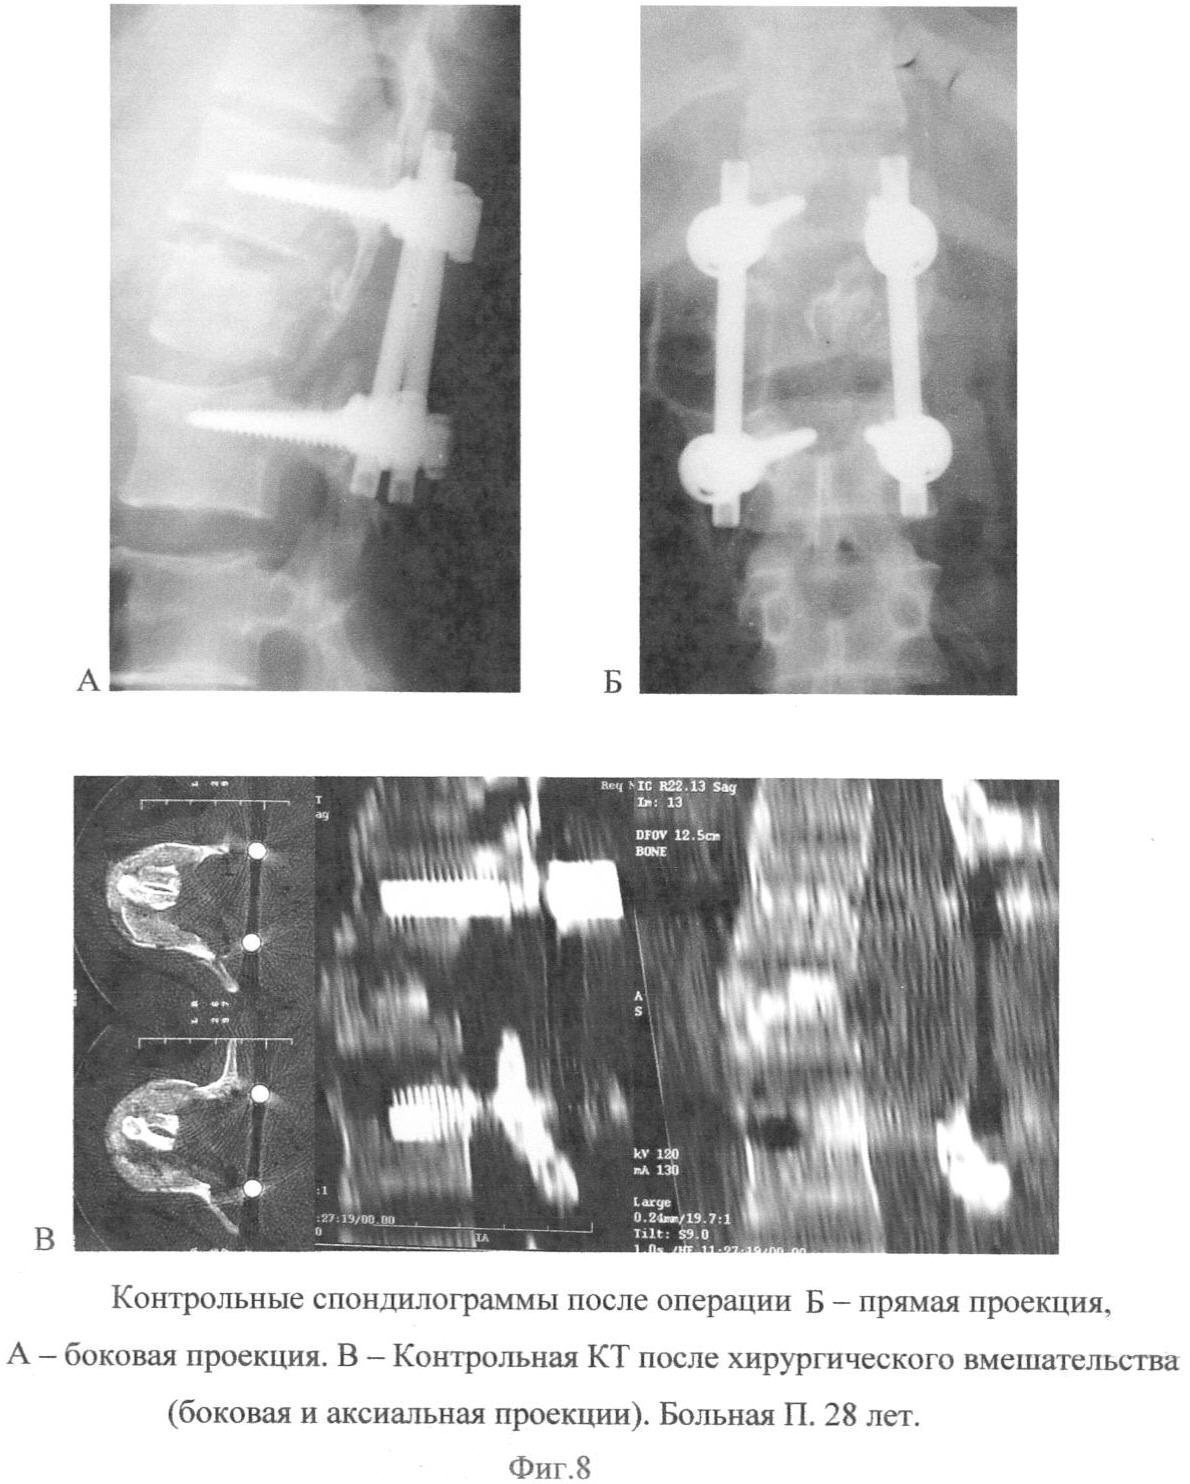

Клинический пример: Больная П., 28 лет. Поступила в клинику с диагнозом: «Закрытый осложненный компрессионно-оскольчатый перелом L1 позвонка. Ушиб, сдавление спинного мозга». Из анамнеза известно, что пострадавшая выпала из окна 2-го этажа. При клинико-неврологическом исследовании был выявлен нижний дистальный парапарез до 4 баллов, нарушение чувствительности по проводниковому типу с уровня L2 сегмента спинного мозга. Нарушение функций тазовых органов по типу задержки. При спондилографии выявлен оскольчатый перелом L1 позвонка (Фиг.7А, Б) с кифотической деформацией на этом уровне. При КТ визуализирован отломок в верхней части тела позвонка, внедренный в просвет позвоночного канала и перекрывающий его более чем на 50% (Фиг.7В).

На контрольных рентгенограммах после операции отмечается положение ауто-трансплантата между телами Th12-L1 позвонков, кифотическая деформация устранена (Фиг.8А, Б). На контрольных КТ подтверждено восстановление размеров позвоночного канала и положение аутотрансплантатов внутри тела сломанного позвонка (Фиг.8В). Операционная рана зажила первичным натяжением. Швы сняты на 11-е сутки.